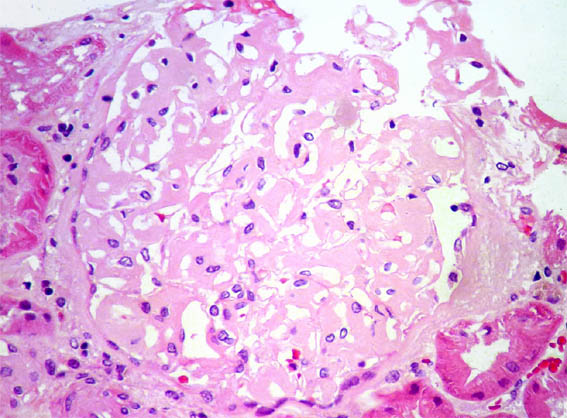

Figure 1.

H&E, X400.